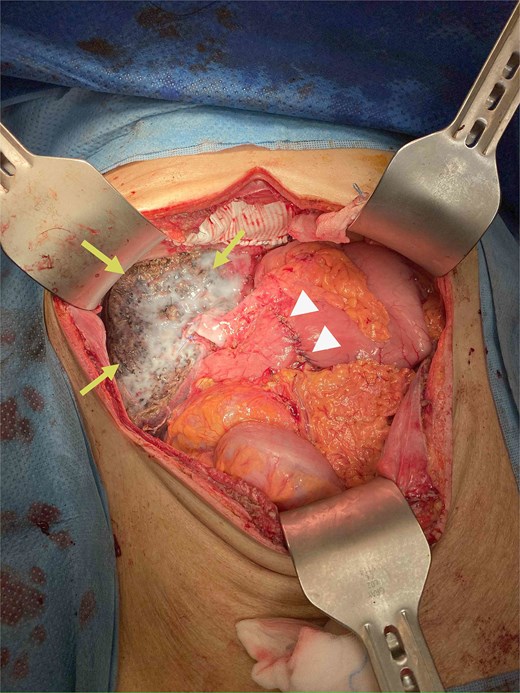

During operation, an exophytic 7 cm segment 4 tumor was found invading superiorly to left hemidiaphragm and pericardium, inferiorly invading to first part of duodenum. A cuff of duodenal wall was removed with tumor and the duodenal defect was closed primarily with 3/0 PDS. Part of the left hemidiaphragm together with pericardium was resected, the heart and left lung were exposed (Fig. 3). The diaphragmatic/pericardial defect was closed with Gore-Tex mesh with single layer continuous 3/0 Prolene (Fig. 4). Air was expelled through an under-water seal catheter placed in the pleural cavity before suture was tightened and tied. Left trisectionectomy was then completed (Fig. 5). The patient developed intra-abdominal collection after surgery which resolved with percutaneous drainage. Pathology confirmed a 7 cm ICC, there was evidence of rupture with abscess formation, and adhesion but no direct invasion to duodenum and diaphragm (Fig. 6). The resection margin was clear. No satellite lesion or microvascular invasion. CEA decreased to normal level after surgery. The patient declined adjuvant chemotherapy.

Operative photo showing the pericardium was removed en bloc with liver tumor, the heart was exposed (arrows).